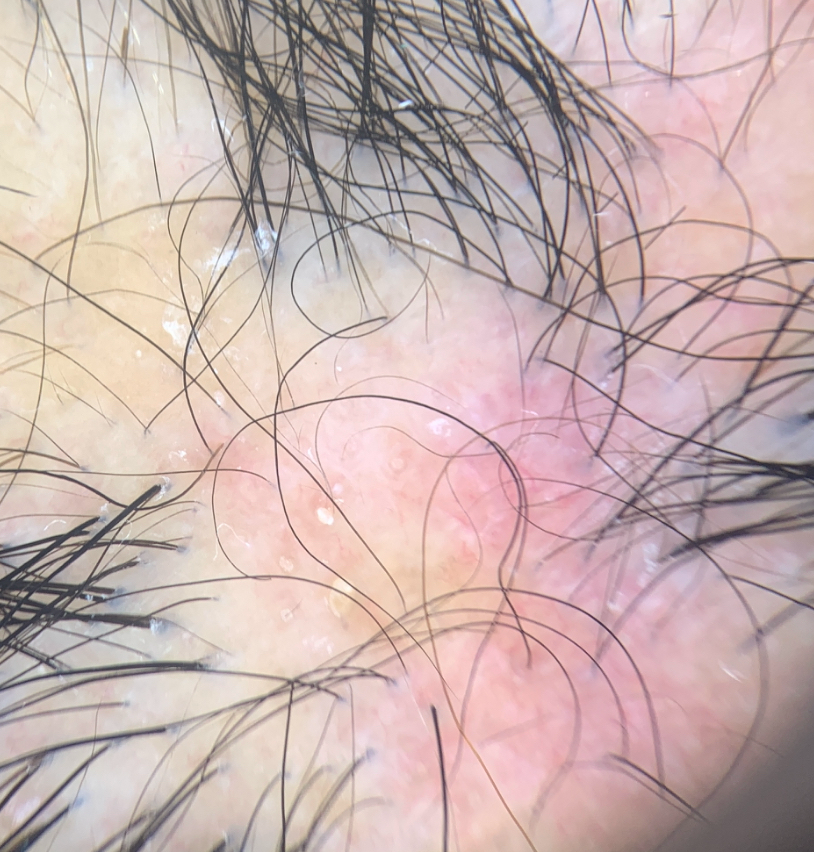

Scalp sarcoidosis in a 43 year old woman. She did not have systemic involvement other than mildly elevated calcium levels. Image from Ghosh A et al. Single lesion of sarcoidosis presenting as cicatricial alopecia: a rare report from India. Int J Trichology . 2014 Apr;6(2):63-6. Image used with creative commons license.

Scalp sarcoidosis in a 43 year old woman. The patient’s other image is shown above. She did not have systemic involvement other than mildly elevated calcium levels. Image from Ghosh A et al. Single lesion of sarcoidosis presenting as cicatricial alopecia: a rare report from India. Int J Trichology . 2014 Apr;6(2):63-6. Image used with creative commons license.

Trichoscopy is helpful. A variety of trichoscopic findings have been described by others including Starace et al and Torres et al.

a) lack of follicular ostia

b) red-orange color (granulomas in the dermis)

c) capillaries (vasodilatation in the papillary dermis)

d) brown dilated ostia (bigger than those of alopecia areata)

e) dystrophic hairs

f) cicatricial skin spots

The orange color with the telangiectasis is thought to be quite a specific skin sign of sarcoidosis.

Trichoscopy of sarcoidosis closely mimicking discoid lupus. Red brown color and telangiectasis can be seen.